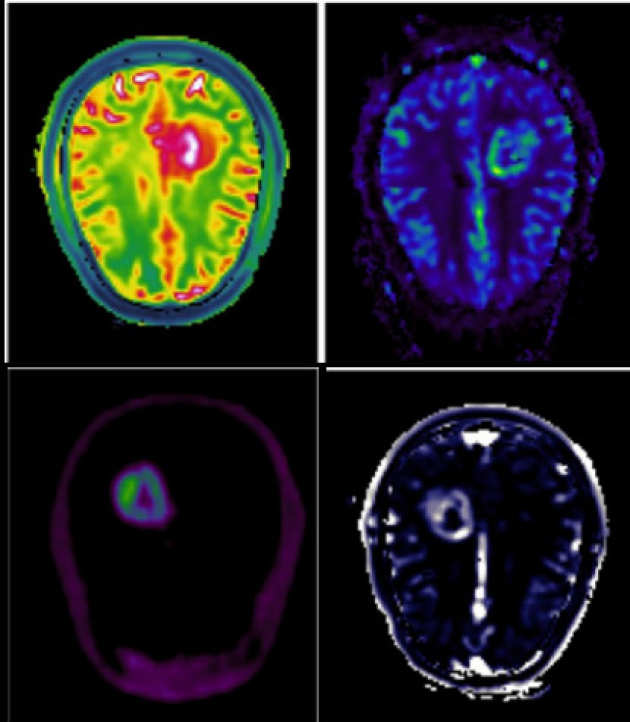

Brain tumour biomarker development

We are investigating imaging biomarkers (diffusion MRI, perfusion MRI, MR Spectroscopy, choline PET) and developing the clinical tools needed to understand brain tumour growth and improve brain tumour diagnosis.

We are investigating imaging biomarkers (diffusion MRI, perfusion MRI, MR Spectroscopy, choline PET) and developing the clinical tools needed to understand brain tumour growth and improve brain tumour diagnosis.

DCE-MRI data modelling

We are applying different pharmacokinetic models to DCE-MRI data to assess blood-brain barrier disruption and leakage in primary brain tumours.

We are applying different pharmacokinetic models to DCE-MRI data to assess blood-brain barrier disruption and leakage in primary brain tumours.

Multiparametric analysis of brain tumours

We are investigating the integration of different imaging (DCE-MRI, DWI-MRI, DSC-MRI and PET) techniques for the characterization of tumour tissue.

We are investigating the integration of different imaging (DCE-MRI, DWI-MRI, DSC-MRI and PET) techniques for the characterization of tumour tissue.